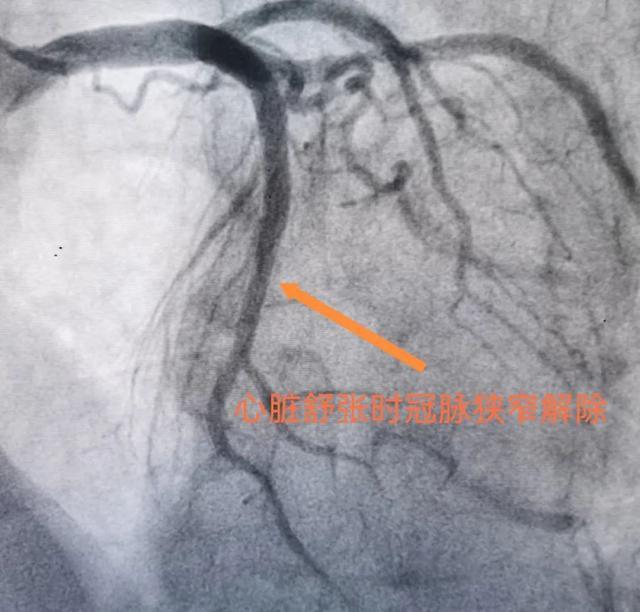

壁冠状动脉在心脏收缩期往往受到心肌组织压迫而管腔缩窄,舒张期时压迫解除而恢复充盈,被称为“挤奶现象”。大部分人都没有症状,当出现了一些胸闷、胸痛的症状到医院检查,尤其是做冠脉CT成像、冠脉造影、冠脉内超声等检查时才会被诊断。